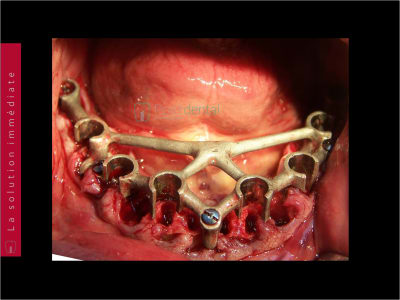

Mon dernier cas de cette année : guide perso a appuis osseux, bridge imprimé maison.

20/12/2022 à 07h52

Enfin, le cas de la semaine précedente. Guide osseux maison, bridge imprimé. On conserve 26 27. Mais les sinus sont assez antérieurs : on sort au niveau des 4 avec les implants angulés. Malgré le fait de faire un mini comblement sinus droit : l'implant passe la crete, rentre dans le sinus, et retrouve l'os en direction nasal, mais on sort quand meme en 14.

Alors pose d'un implant dans l'alvéole de la 15, aucune stabilité, comblement. A utiliser pour le bridge définitf.

Cas clinique du Docteur Marc REGRAIN - mise en charge immédiate MCI 001.jpg

Cas clinique du Docteur Marc REGRAIN - mise en charge immédiate MCI 002.jpg

Cas clinique du Docteur Marc REGRAIN - mise en charge immédiate MCI 003.jpg

Cas clinique du Docteur Marc REGRAIN - mise en charge immédiate MCI 004.jpg